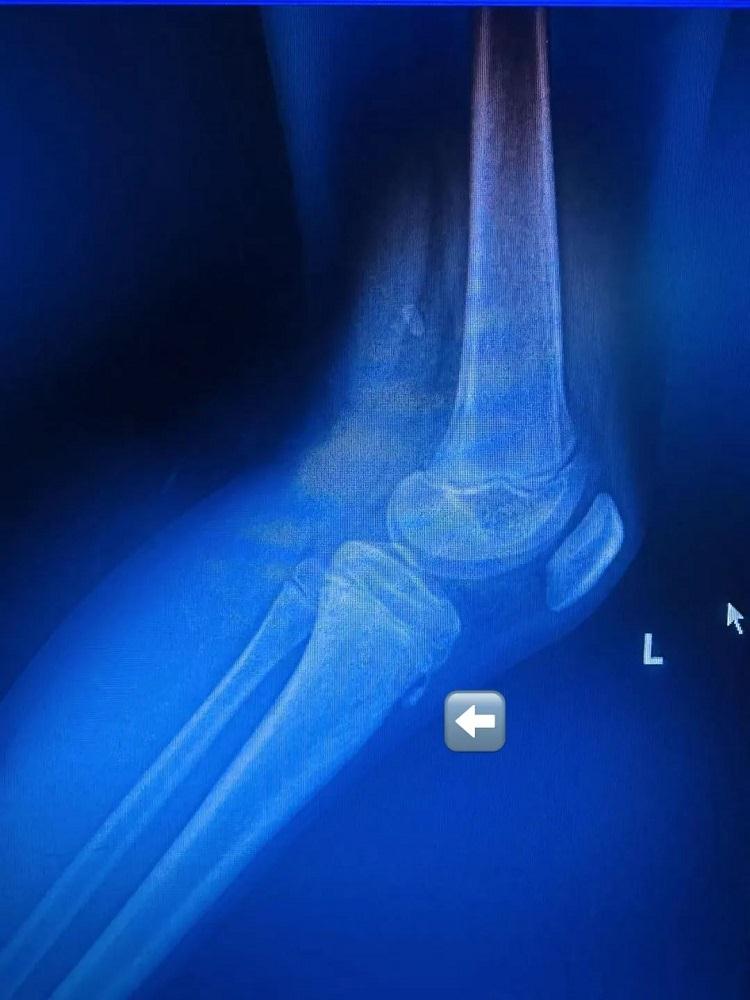

經過運動損傷防治門診楊晟興主治醫(yī)師全面的體格檢查與拍片檢查,小黃原來是患上了一種名為“脛骨結節(jié)骨骺炎”的疾病。通過針對治療與適當休息,他的膝關節(jié)疼痛癥狀得到有效緩解,脛骨結節(jié)骨骺炎也得到了妥善醫(yī)治。令人意外的是,像小黃這樣的小運動員并非個例,擊劍高手、羽毛球健將等運動少年也頻頻中招。

在運動損傷防治門診,經常會發(fā)現(xiàn)有孩子膝蓋痛,膝蓋前方還可以摸到凸起的骨頭,家長擔心是否長了“不好的東西”。經過檢查,發(fā)現(xiàn)這些孩子大部分是患上了專病門診常見的疾?。骸懊劰墙Y節(jié)骨骺炎”或“脛骨結節(jié)骨軟骨病”。

脛骨結節(jié)骨骺炎是青少年群體中較為常見的一種膝關節(jié)疾病。其發(fā)病機制主要是脛骨結節(jié)骨骺在髕腱反復牽拉下受損。該病多見于 11 - 15 歲的青少年,特別是那些熱愛運動的男孩,主要表現(xiàn)為脛骨結節(jié)部位疼痛與腫脹。

脛骨結節(jié)是膝蓋下方脛骨頂端的一個骨性凸起,是髕腱(連接膝蓋骨與小腿骨的肌腱)的附著點。青少年時期,此處的骨骺(骨骼生長板)尚未完全閉合,處于脆弱階段。當髕腱反復牽拉脛骨結節(jié),可能導致局部微小損傷、炎癥甚至骨骺撕裂,從而引發(fā)疼痛和腫脹。